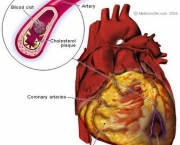

Ataque cardíaco ocorre quando uma artéria coronária se torna bloqueadas de modo simultâneo. O bloqueio repentino rouba certa porção do músculo do coração e fornecimento vital do sangue. De fato acontece a morte do músculo. O bloqueio súbito da artéria coronária é causada por ruptura de placa na artéria que produz variedade de condições clínicas, incluindo ataques cardíacos e angina instável, agrupados sob o nome de síndrome coronariana aguda (SCA). Todas as formas de SCA são emergências médicas, tratados com medicamentos, angioplastia, implante e cirurgia para restaurar o fluxo normal de sangue através da artéria bloqueada. Se o fluxo pode ser restaurado dentro de poucas horas, danos permanentes podem ser minimizados.

Infarto do miocárdio resulta da interrupção parcial do fornecimento de sangue a uma parte do músculo cardíaco, fazendo com que as células do coração sejam danificadas até morrer. Isto acontece em geral devido à oclusão (bloqueio) de uma artéria coronária após a ruptura da placa aterosclerótica vulnerável, conjunto estável de colesterol, ácidos gordos e os glóbulos brancos do sangue na parede da artéria. Resultante de isquemia (restrição no fornecimento de sangue) e consequente falta de oxigênio. Caso deixada sem tratamento por um período de tempo suficiente pode causar danos ou morte (infarto) do tecido muscular do coração (miocárdio). Os sintomas típicos de infarto agudo do miocárdio incluem súbita dor no peito (geralmente irradia para o braço esquerdo ou do lado esquerdo do pescoço), falta-de-ar, náuseas, vômitos, palpitações, sudorese e ansiedade. As mulheres podem experimentar sintomas típicos menores do que os homens, caso da falta de ar, fraqueza, sensação de indigestão e fadiga. Proporção considerável de infartos do miocárdio (22-64%) “silenciosa”, isto é, sem dor no peito ou outros sintomas. Entre os testes de diagnóstico para a detecção de danos ao músculo cardíaco estão: Eletrocardiograma (ECG), ecocardiograma e vários exames de sangue. Os marcadores utilizados com frequência são de creatina e fração dos níveis de troponina.